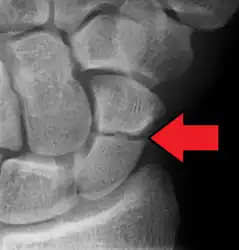

| An X-ray showing a fracture through the waist of the scaphoid | |

Scaphoid fractures are often diagnosed by PA and lateral X-rays. However, not all fractures are apparent initially.[7] Therefore, people with tenderness over the scaphoid (those who exhibit pain to pressure in the anatomic snuff box ) are often splinted in a thumb spica for 7–10 days at which point a second set of X-rays is taken.[7] If there was a hairline fracture, healing will now be apparent. Even then a fracture may not be apparent. A CT Scan can then be used to evaluate the scaphoid with greater resolution. The use of MRI, if available, is preferred over CT and can give one an immediate diagnosis.[9] Bone scintigraphy is also an effective method for diagnosis fracture which do not appear on Xray.[10]

A subtle scaphoid fracture -

A more obvious scaphoid fracture on a scaphoid view X ray -